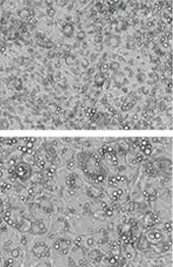

체지방 감소 엑소좀( T-Exo) 처리 시 지방 감소 효과 확인

• 1. 백색지방 세포 이미지

• 2. 지질 감소 효과 (ORO Stain)